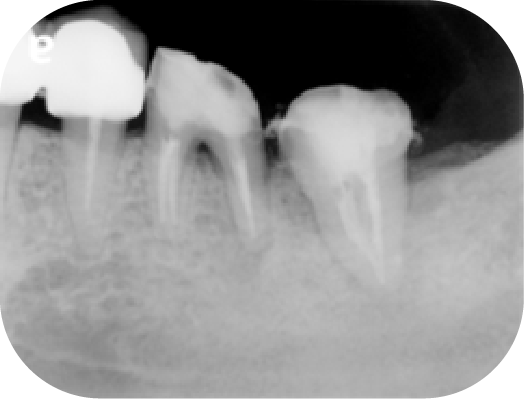

上圖中第一大臼齒兩個牙根皆因為根管內的感染造成根尖周圍炎(紅線中黑黑的地方),在根管治療後追蹤一年可發現骨頭都已經恢復正常的樣子